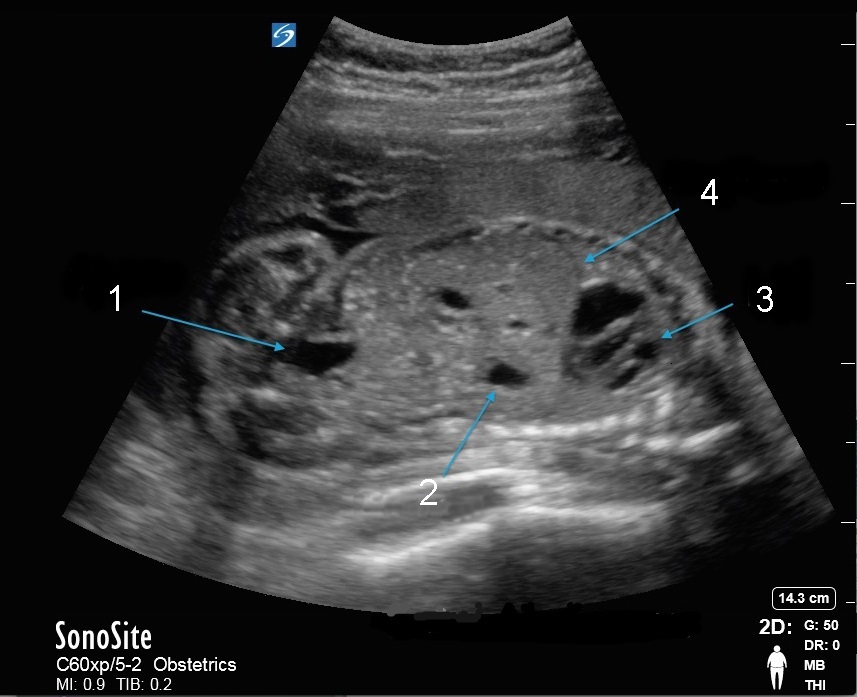

骨盤胎児腹部画像

膀胱

胃

HRT

横隔膜